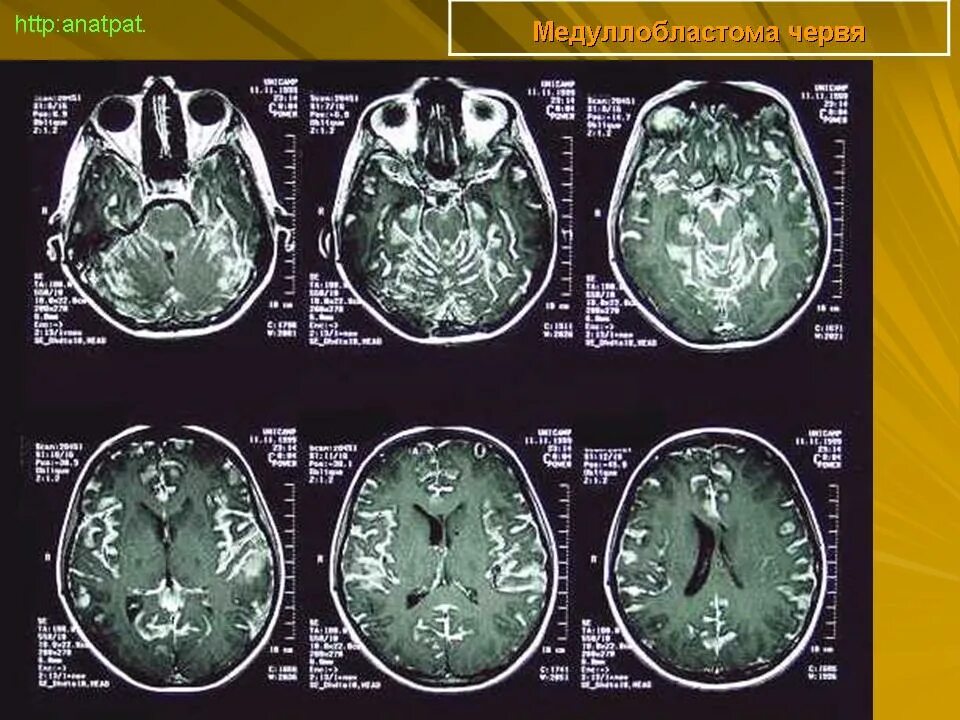

Медуллобластома это